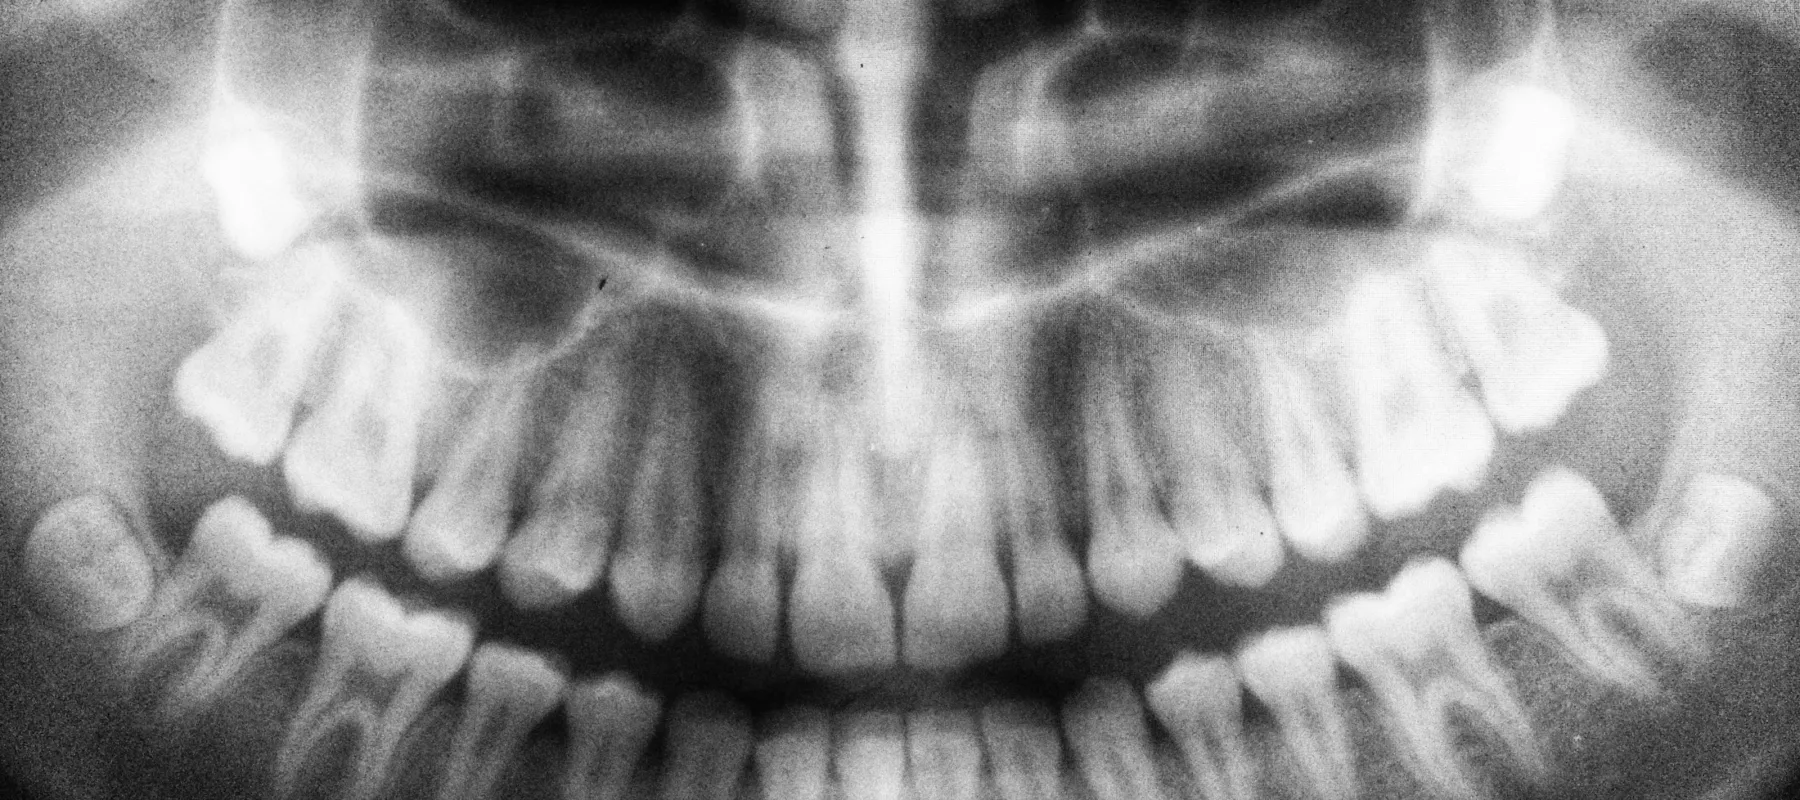

Black and white panoramic dental X-ray showing full adult teeth and jaw structure

Digital X-Rays

We use low-radiation imaging that delivers crystal-clear pictures in seconds. We can spot what needs attention and walk you through it together. You don't have to deal with the old-school wait or mess of film.

What are the benefits of digital X-rays over traditional ones?

Digital X-rays offer faster image capture with significantly less radiation exposure than traditional film. They're more comfortable and provide high-resolution images almost instantly. We can diagnose problems earlier and plan treatment more effectively. Plus, they're better for the environment since they don't require film or chemicals.